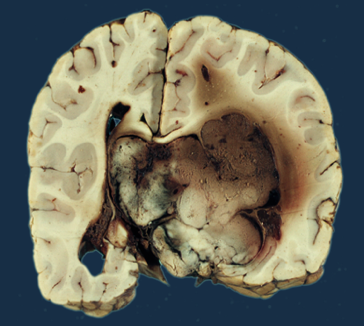

Brodawczak splotu naczyniówkowego to łagodny nowotwór, który rozwija się w obrębie splotu naczyniówkowego, struktury odpowiedzialnej za produkcję płynu mózgowo-rdzeniowego. Splot naczyniówkowy znajduje się w komorach mózgowych, a jego główną funkcją jest wytwarzanie płynu, który otacza i chroni mózg oraz rdzeń kręgowy. Brodawczaki splotu naczyniówkowego mogą występować w różnych lokalizacjach, najczęściej w komorach bocznych mózgu.

Choroba ta występuje najczęściej u dzieci, zwłaszcza u niemowląt, ale może również występować u dorosłych. Chociaż brodawczaki splotu naczyniówkowego są zazwyczaj łagodne i nie mają tendencji do przerzutów, ich obecność może prowadzić do różnych powikłań. Zwiększenie objętości nowotworu może powodować wzrost ciśnienia wewnątrzczaszkowego, co z kolei może prowadzić do objawów neurologicznych, takich jak bóle głowy, wymioty, a nawet problemy z równowagą i koordynacją.

W przypadku diagnozy brodawczaka splotu naczyniówkowego, kluczowe jest monitorowanie jego rozwoju oraz ocena potencjalnych objawów. W niektórych przypadkach, gdy nowotwór nie powoduje znaczących problemów zdrowotnych, lekarze mogą zalecać jedynie obserwację. W sytuacjach, gdy brodawczak staje się problematyczny, możliwe jest zastosowanie leczenia chirurgicznego w celu usunięcia zmiany.